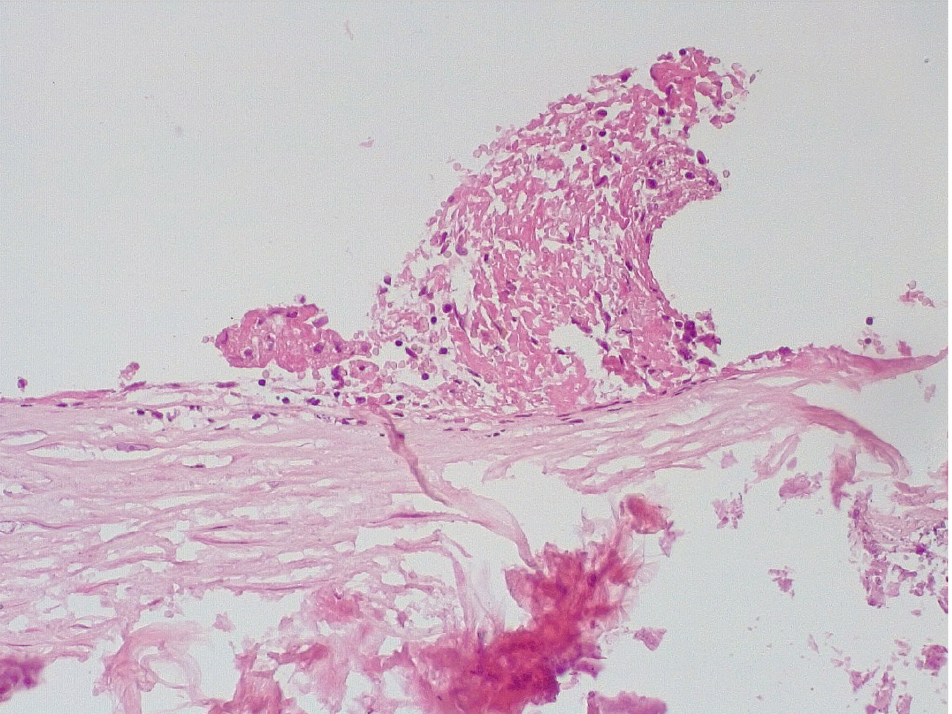

Патоморфологическое исследование стенок КА в ранние сроки после стентирования выявило характерные особенности. В течение первых 3 дней после стентирования в стенке КА имелась атерома с признаками геморрагий. Эндотелий был на большем протяжении разрушен, с признаками десквамации, с окружающей очаговой лейкоцитарной инфильтрацией. Вокруг атеромы, со стороны медии и адвентициальной оболочки, отмечалась умеренновыраженная лимфоцитарная инфильтрация (рис. 1).

Рис. 1. В стенке атеромы КА – геморрагии, умеренновыраженная лимфоцитарная инфильтрация медии и адвентиции. Десквамация эндотелия с очаговой лейкоцитарной инфильтрацией (1–3-и сутки). Окраска гематоксилином-эозином. Ув. ×100